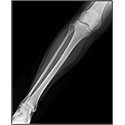

Interactive Radiology